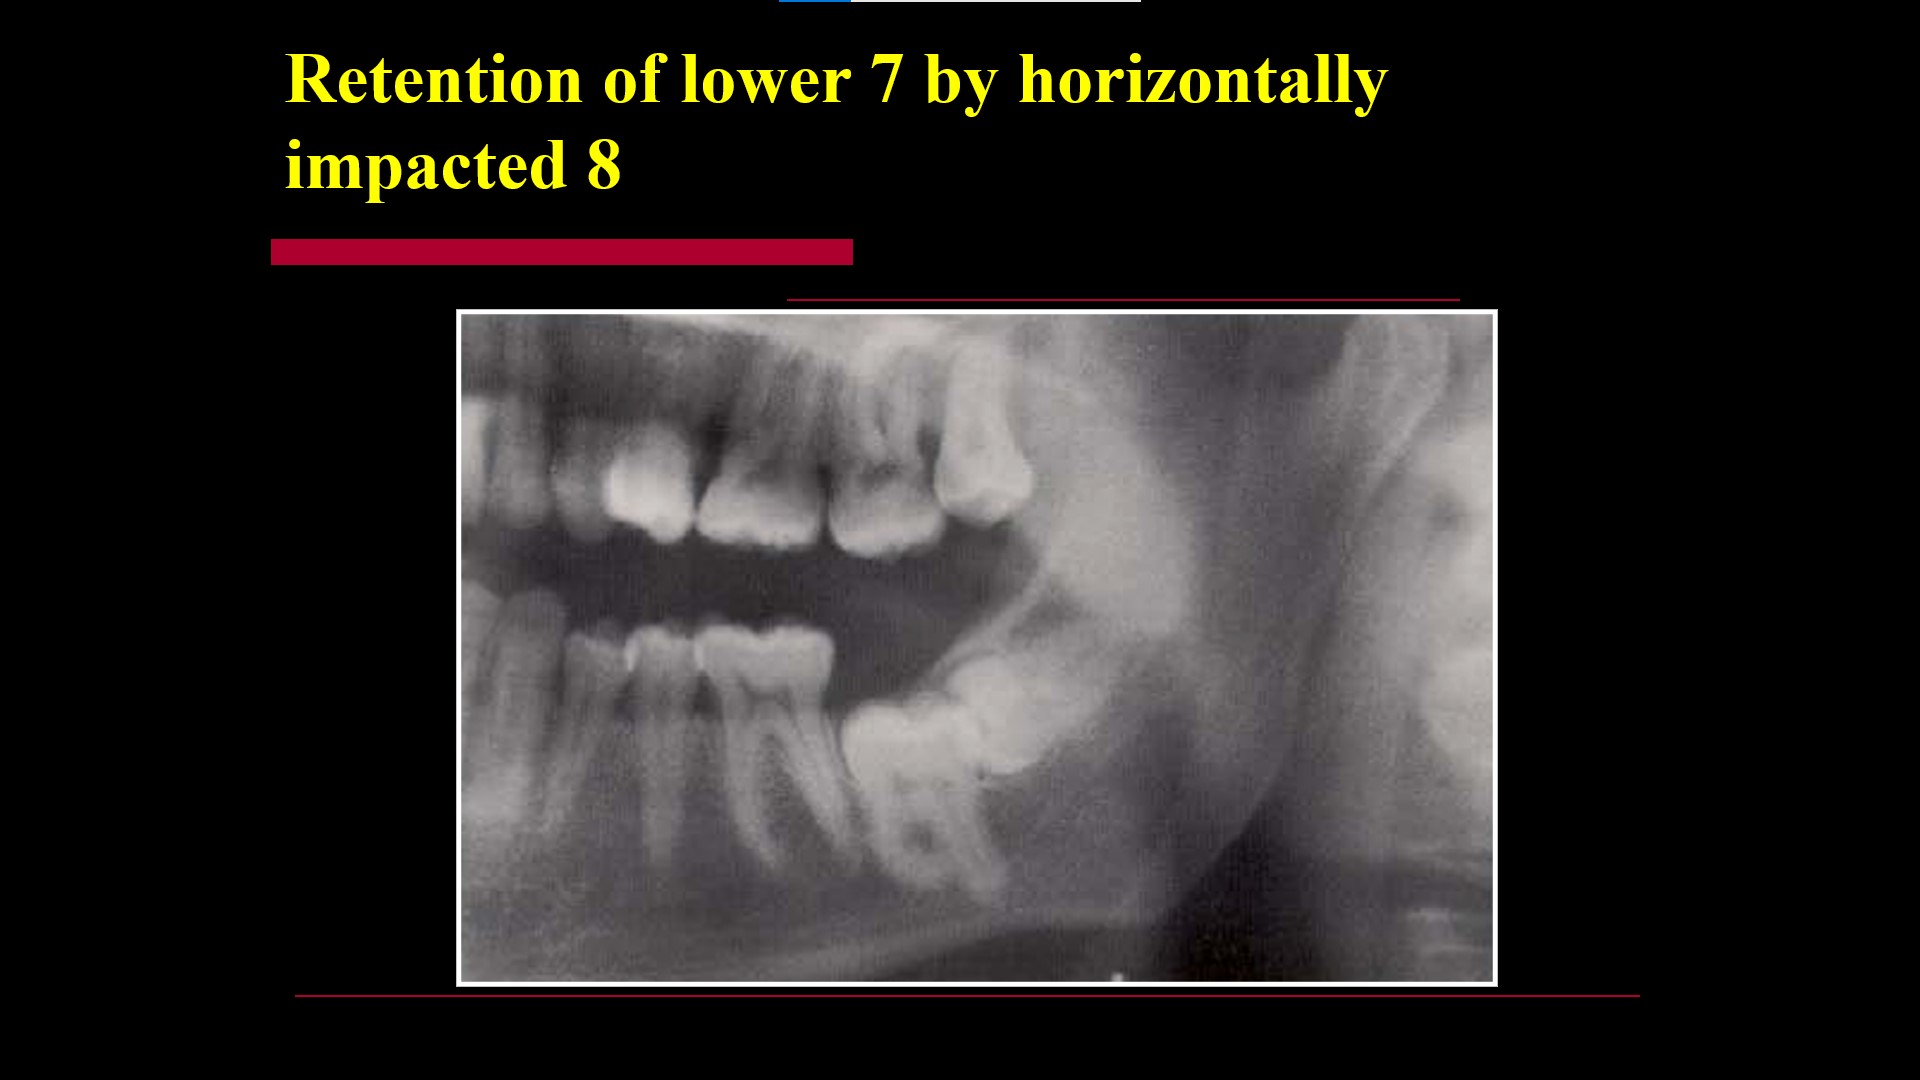

Impacted teeth